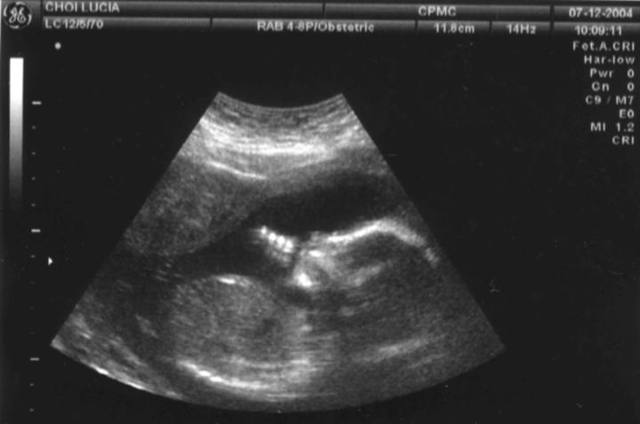

• Semana 12

Semana 12

Por primera vez vas a sentir a tu feto, cuyos movimientos comienzas a notar. Podrás oír los latidos de su corazón. También se puede confirmar por ecografía el sexo.